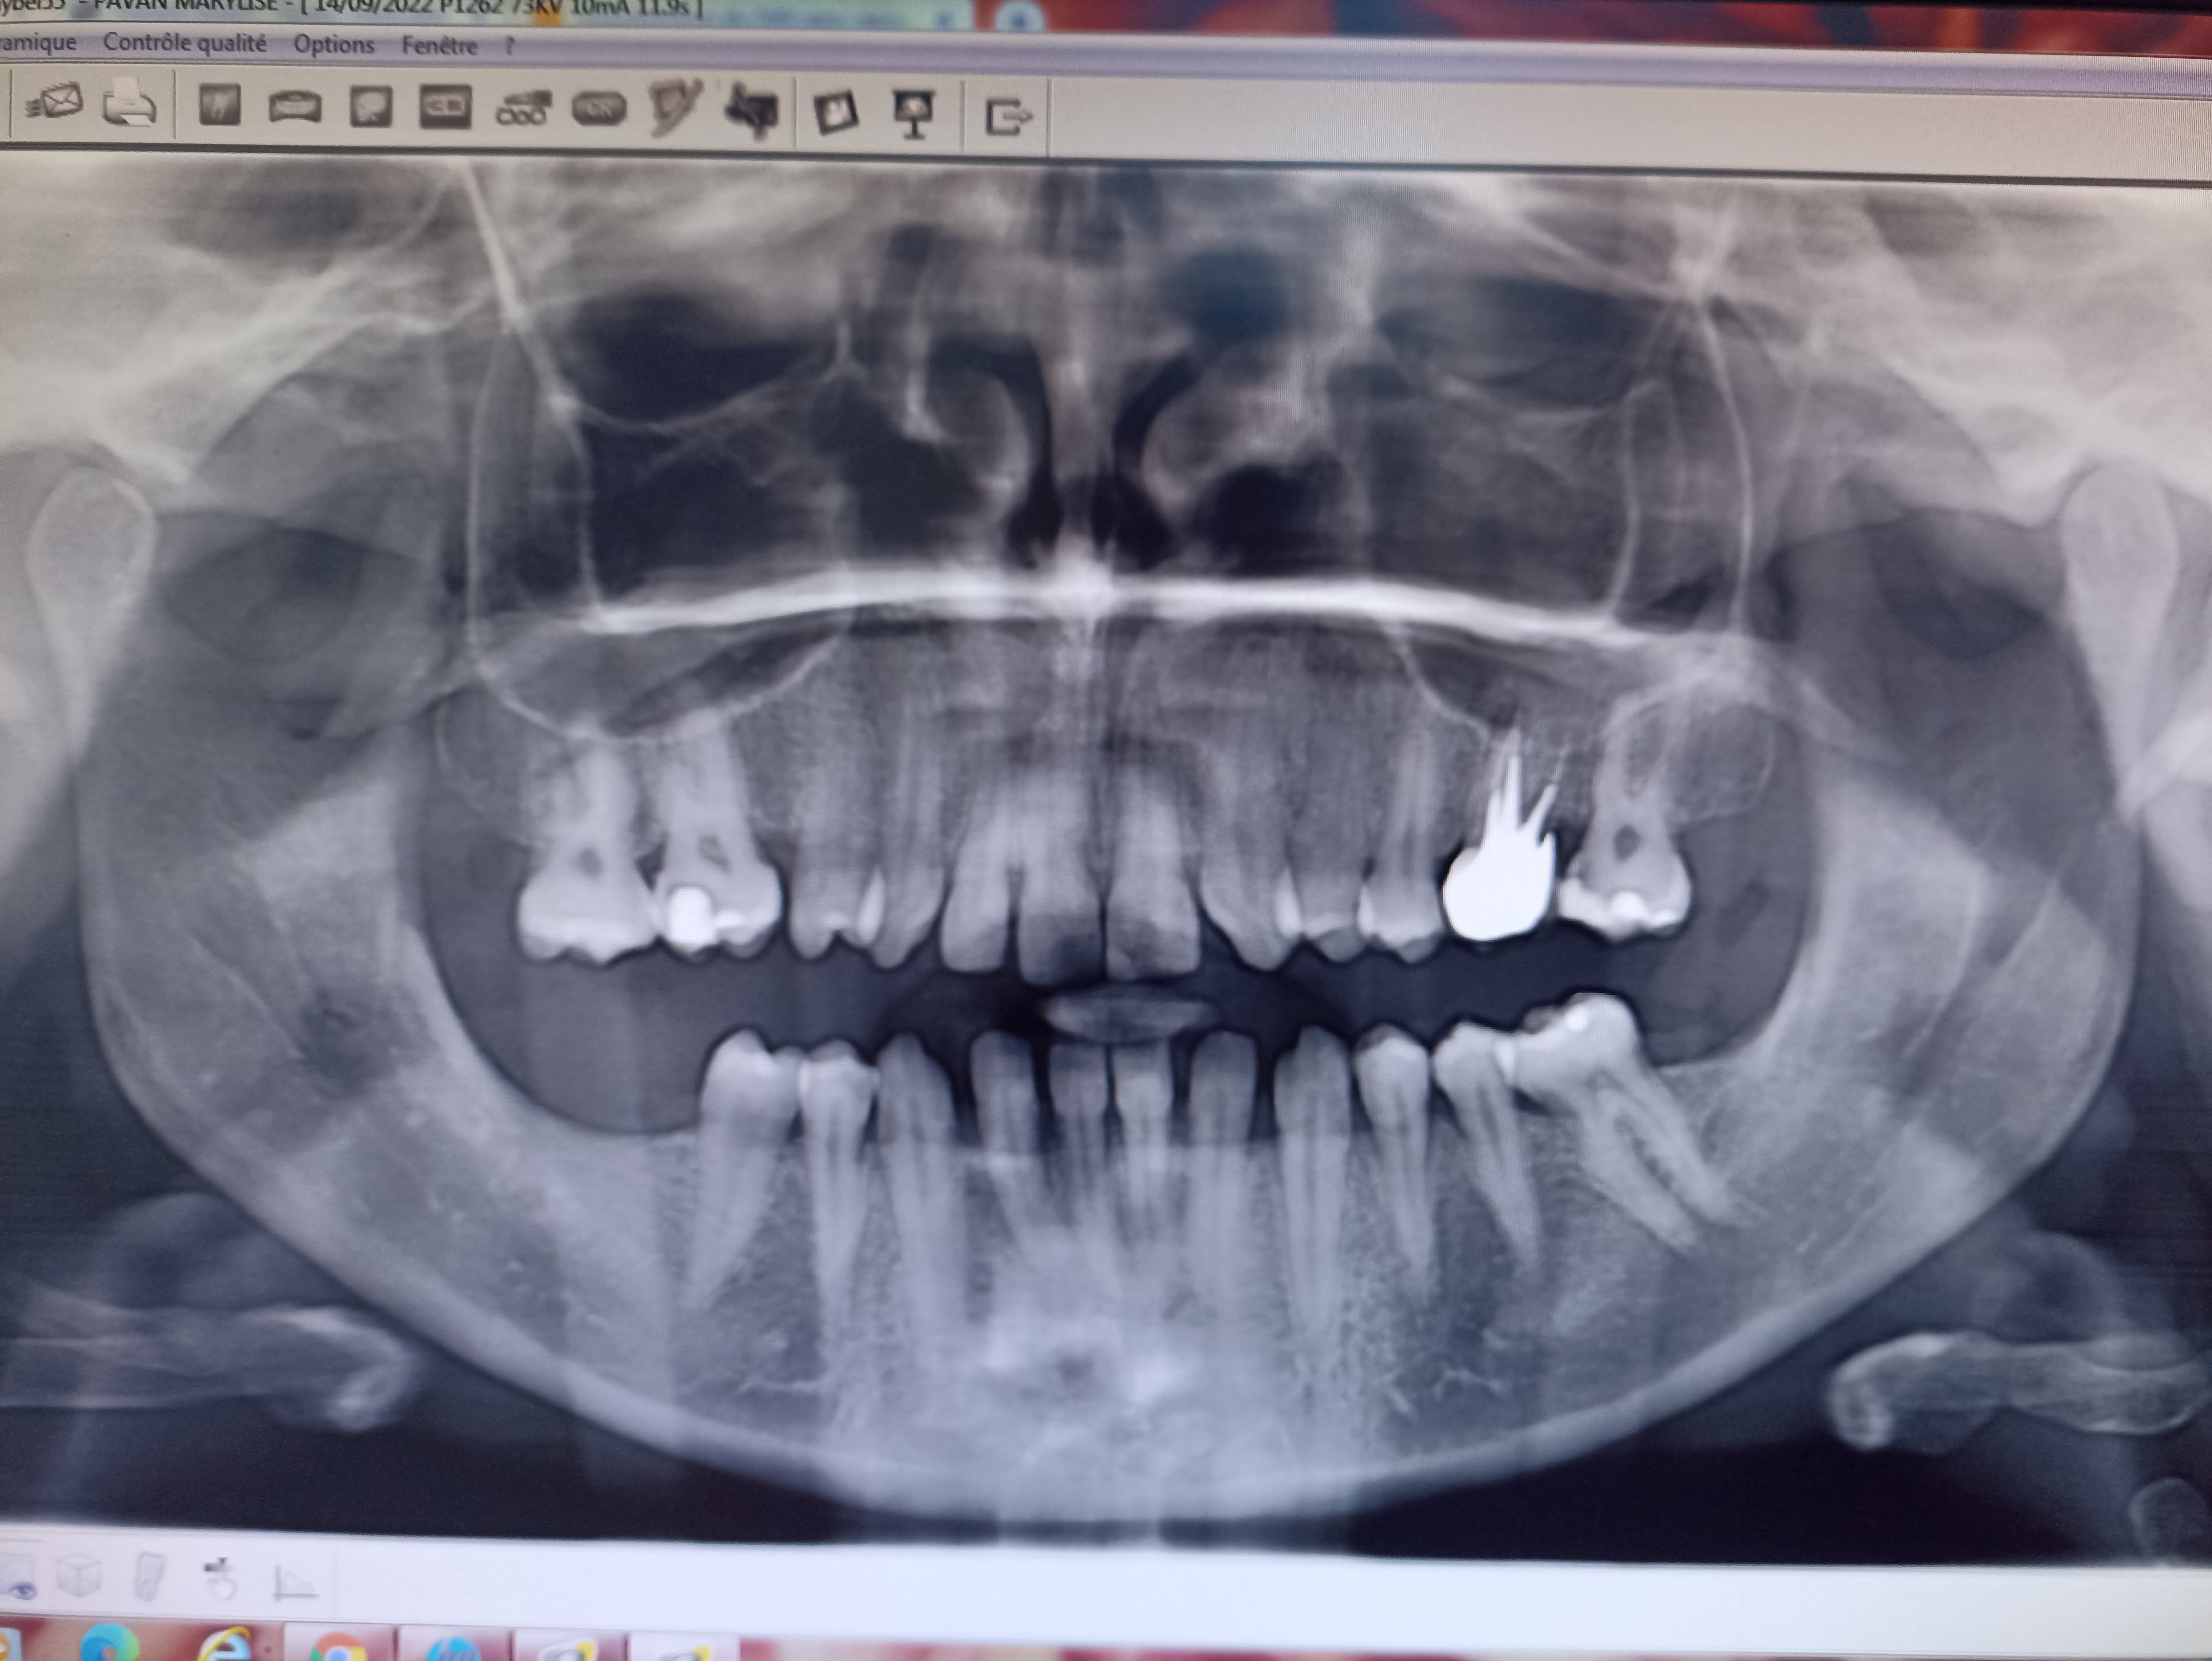

Voilà la pano. De ce qu'elle m'a dit, l'absence des molaires serait d'ordre agenesique

Y'a quand même un soucis sur la 36, il faudrait une rétro pour mieux voir le Pb.